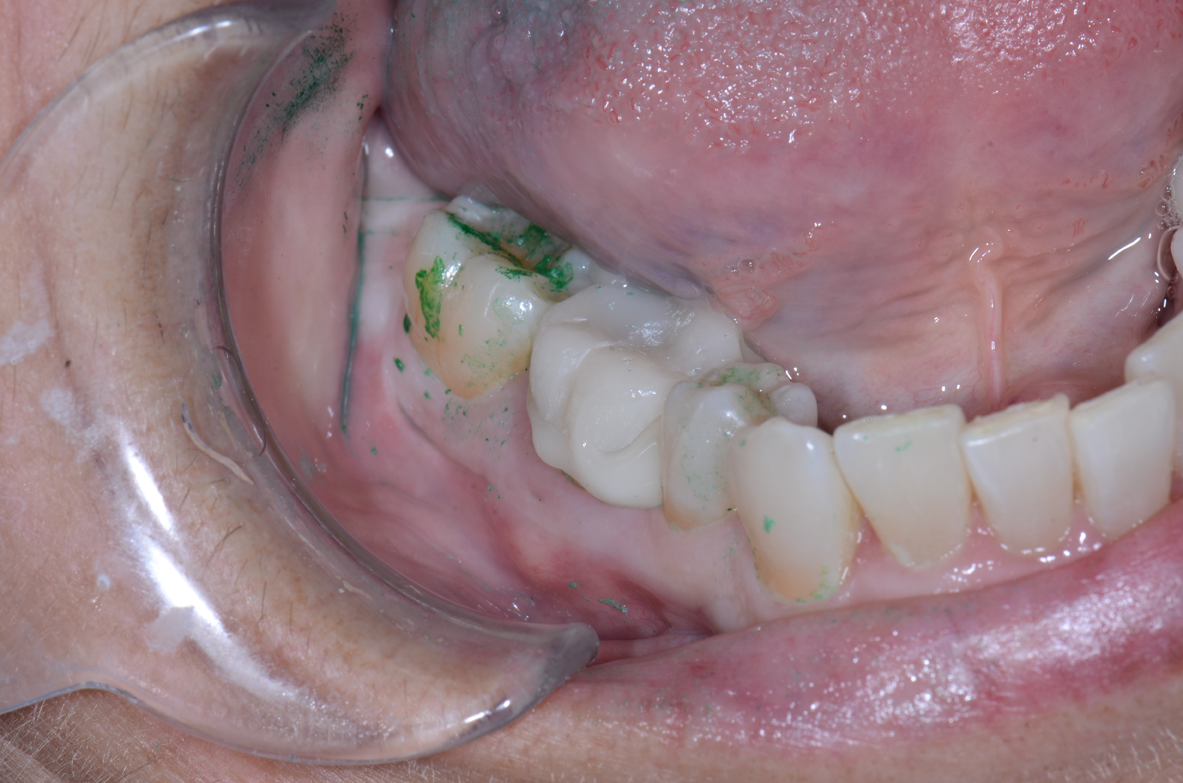

2. Dry the prepared tooth and apply a separator or lubricant-like glycerin over any resin or composite-based materials that were placed during that day’s procedure. Express a small amount of material before placing a new mixing tip. Then, dispense the TempoCem ID into the provisional and seat the restoration (Figs. 8-11).

Fig. 10 Fig. 11 Fig. 12

3. Apply pressure and use an explorer to determine whether or not the provisional is fully seated. Cure the material with an LED curing light for no more than one to two seconds from the lingual and repeat on the buccal. The material will now peel off easily and excess can be removed with an explorer or scaler (Figs. 12-15).